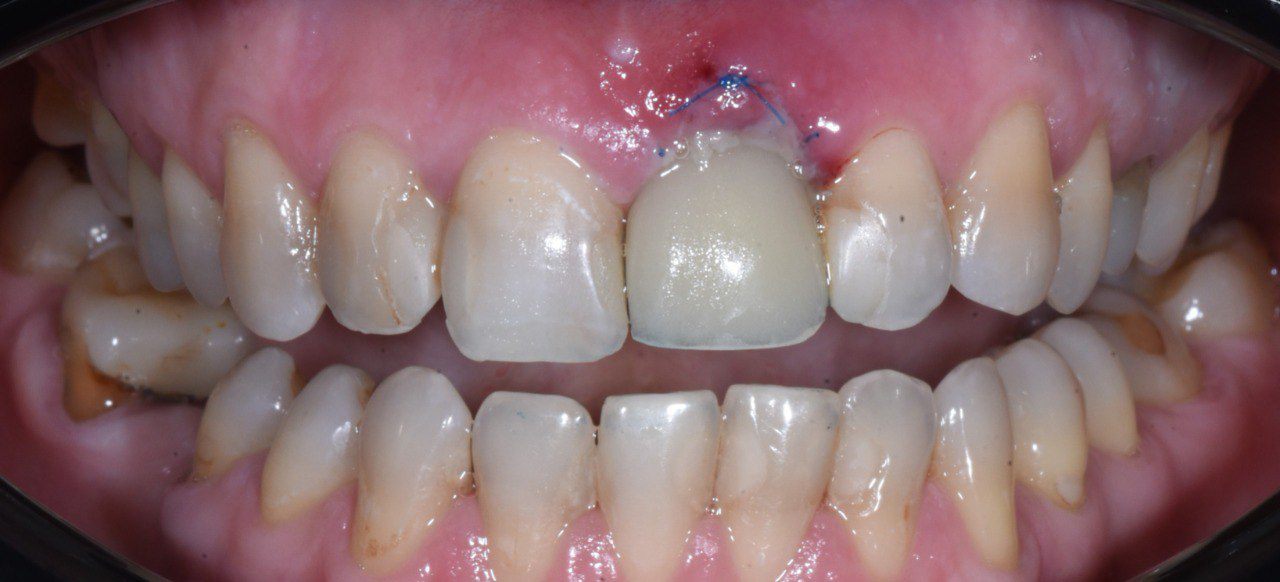

Имплантация сломанного переднего зуба с немедленным протезированием коронкой в зоне улыбки